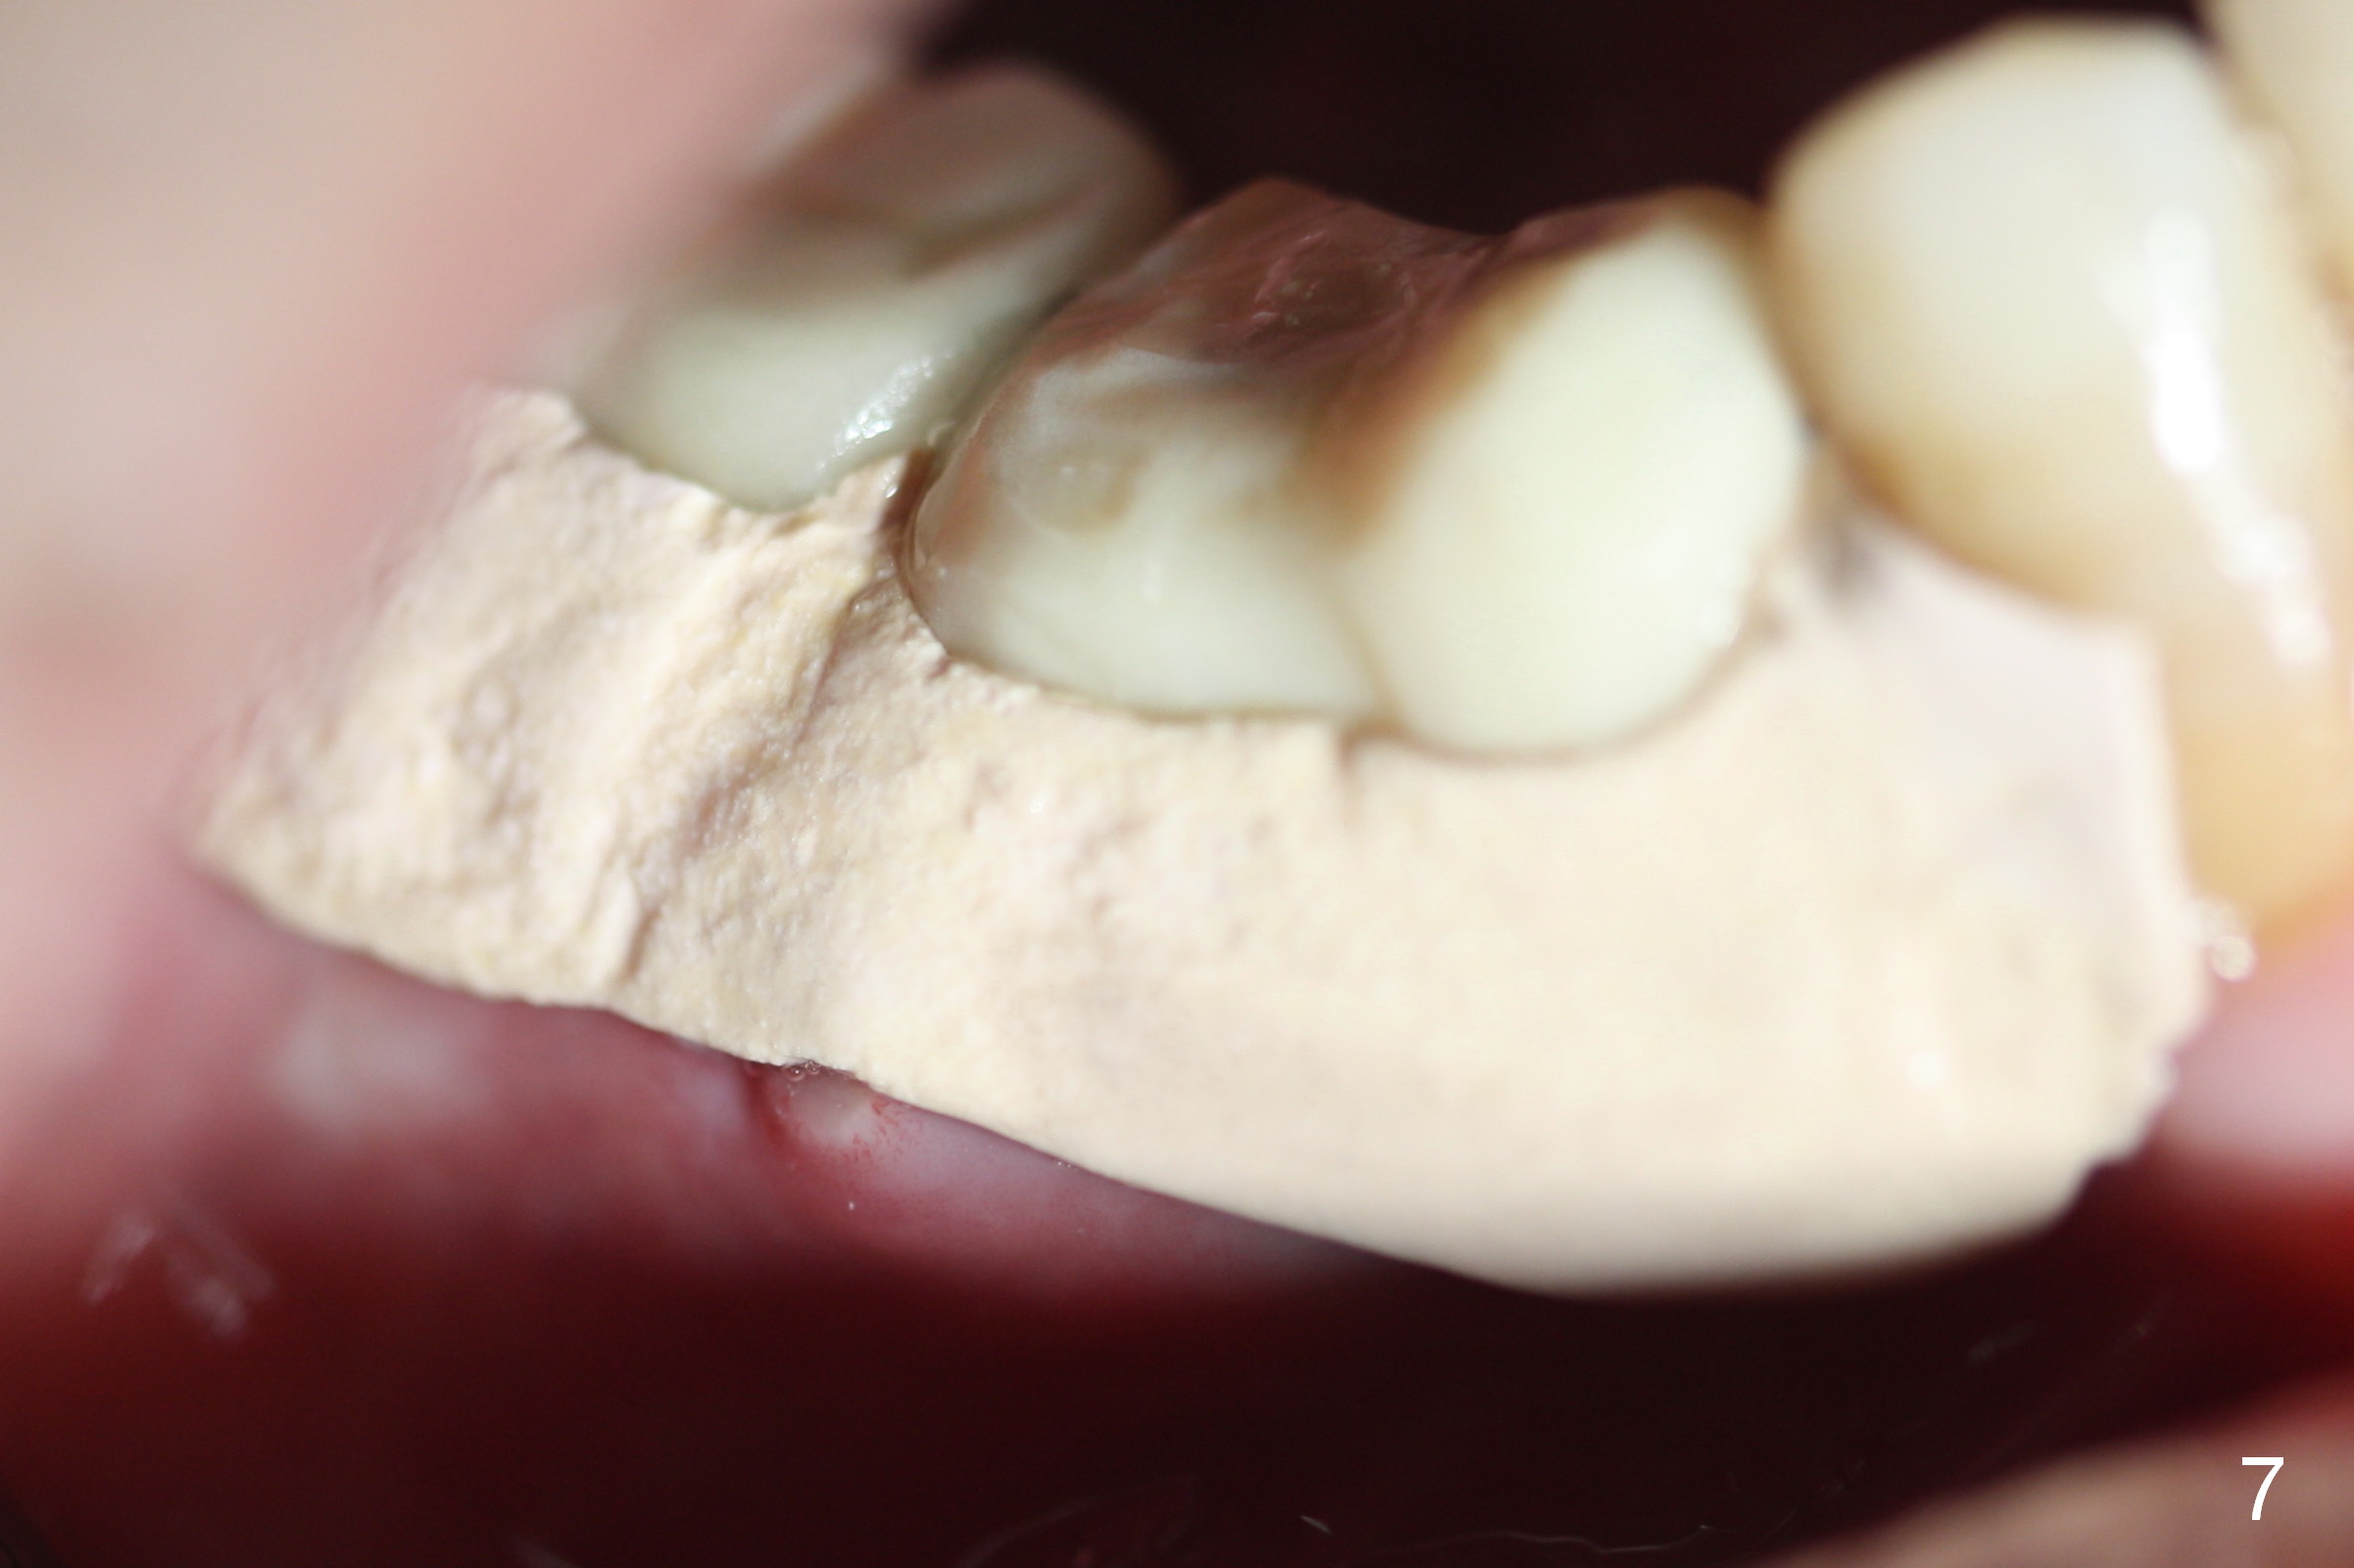

The perio dressing remains in place 1 week postop (Fig.7). After its removal, the wound is healing (Fig.8).